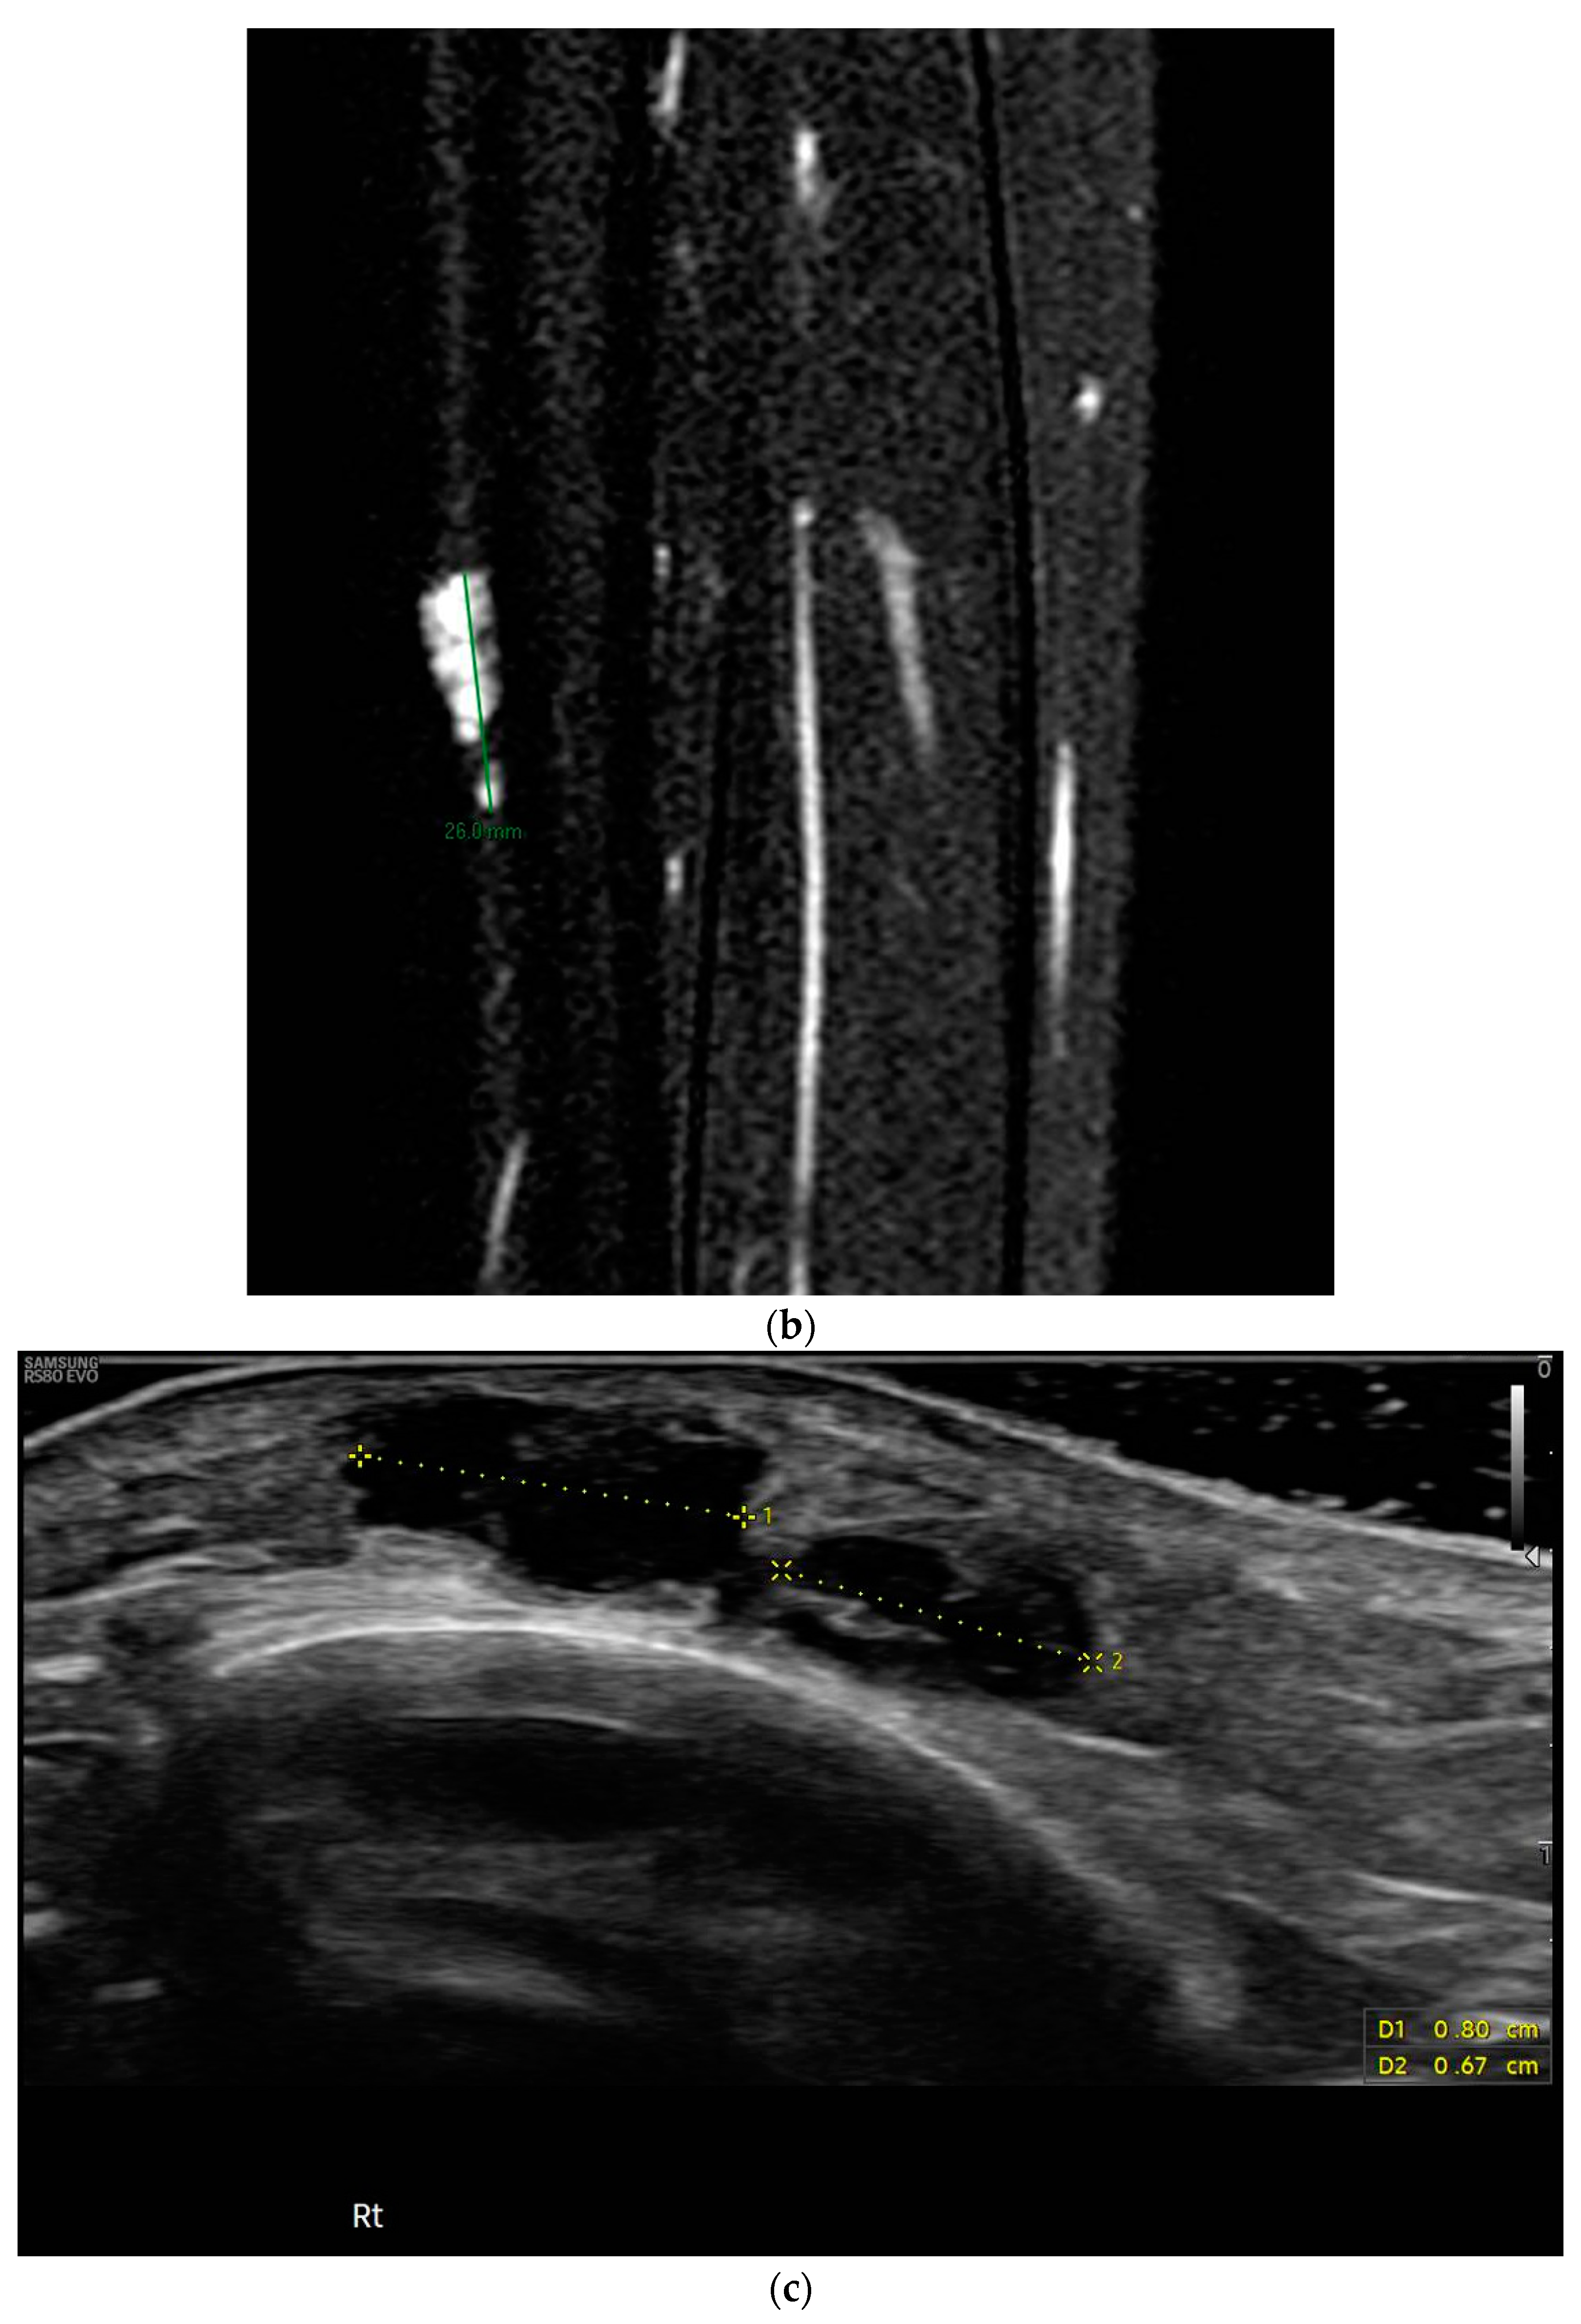

- Tafti, D.A.; Dearborn, M.C.; Ornoff, A.; Moeck, A.R.; Cecava, N.D. Nerve Sheath Myxoma in the Lower Extremity: A Rare Case with Description of Magnetic Resonance Imaging and Sonographic Findings. Am. J. Case Rep. 2021, 22, e927922. [Google Scholar] [CrossRef] [PubMed]